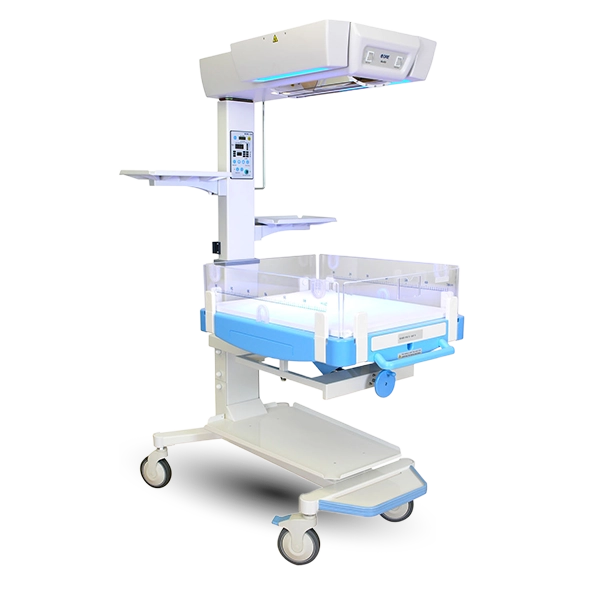

Bubble CPAP Machine Manufacturers

Alxa Medical Technology LLP is a specialized Bubble CPAP Machine Manufacturers in Noida, focused on delivering end-to-end neonatal and critical care medical equipment for modern healthcare facilities. Our comprehensive product range includes Nasal Prongs and Nasal Masks for safe oxygen delivery, advanced Ventilators for controlled respiratory support, and precision-based Syringe Pumps and Infusion Pumps for accurate medication and fluid administration. Each device is designed to meet the critical demands of NICUs and ICUs, ensuring reliability, ease of use, and consistent performance. By combining innovative engineering with medical-grade materials, we manufacture equipment that supports effective clinical decision-making and improved patient care.

Ventilator Suppliers in Uttar Pradesh

As established Ventilator Suppliers in Uttar Pradesh, Alxa Medical Technology LLP provides healthcare institutions with a complete ecosystem of respiratory and infusion solutions. From initial oxygen therapy using Nasal Prongs and Nasal Masks, to advanced mechanical ventilation with Ventilators, and controlled infusion through Syringe Pumps and Infusion Pumps, our products are designed to function together seamlessly. We prioritize timely supply, quality assurance, and dependable service support, enabling hospitals to maintain uninterrupted critical care operations. Our solutions are trusted for their compatibility, durability, and adaptability in high-pressure clinical environments.